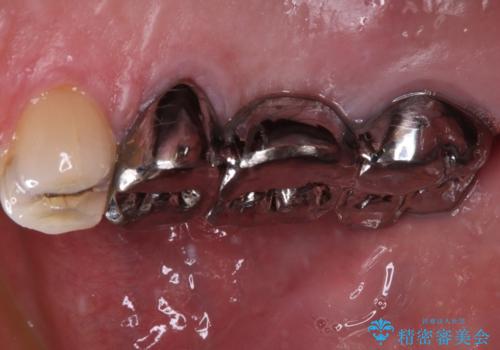

- 奥歯のブリッジに違和感があるとのことで来院された患者様です。

土台となっている最後方の歯に痛みがあるようで、むし歯処置あるいは根管治療を行う前提で金属ブリッジを除去することとしました。

銀歯に隠れていて術前のレントゲンでははっきりと分かりませんでしたが、元々非常に大きなむし歯があったようで、銀歯の中で神経組織が壊死を起こしていました。

速やかに根管治療を行い、無事に痛みを取り除くことができました。